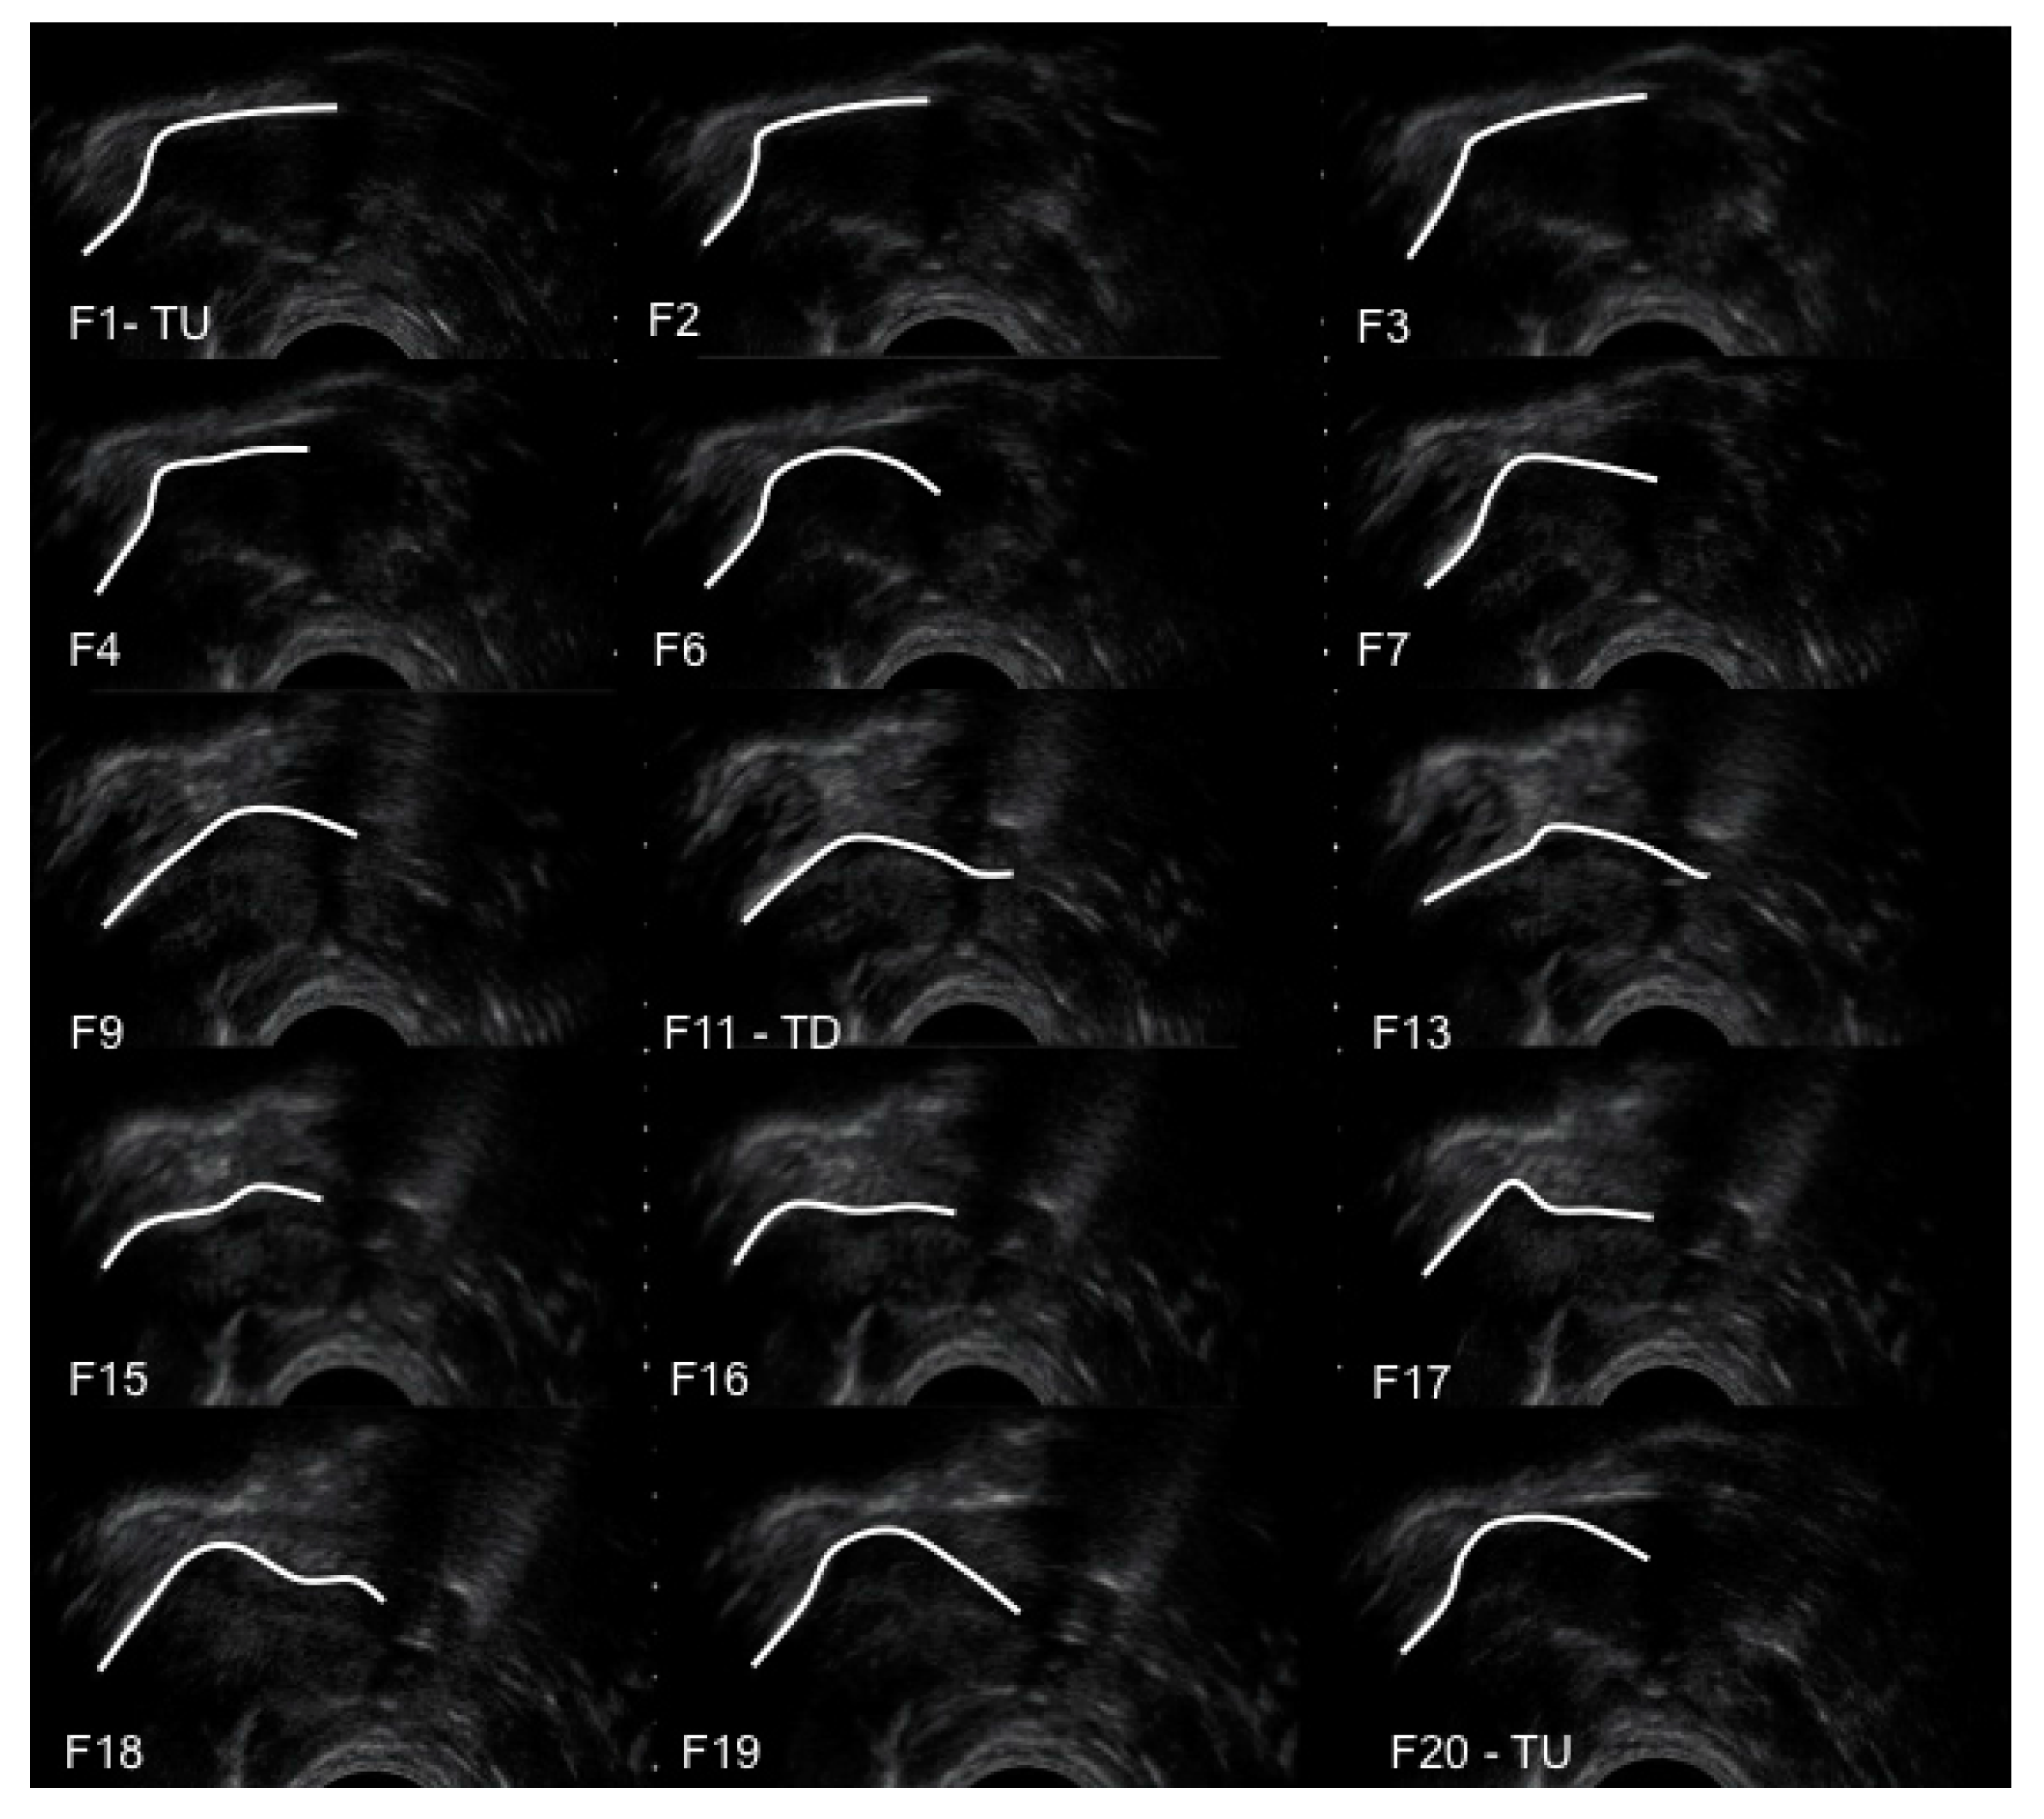

The temporal sequence of tongue movement over a suck cycle is shown in an ultrasound image sequence for a control infant in Figure 2. From F1 (tongue up) to F9 the tongue moved inferiorly with the mid-tongue showing most displacement as it moved away from the HSPJ. At F11 (tongue down) the mid-tongue was at its lowest point. From F11 to F20 the mid-tongue rose sequentially in an anterior posterior fashion. The anterior tongue of several infants was seen to rise slightly before the mid-tongue had reached the nadir, but there was no consistent difference between Control group and Pain group.

Figure 2. Sequential submental ultrasound frames (F1 to F20) of the infant intra-oral cavity with the tongue contour marked in white. TU, tongue up; TD, tongue down.

During nutritive sucking the greatest degree of tongue movement (7.2 mm for Control group) occurred where the mid-tongue lowered from the HSPJ as vacuum within the oral cavity increased and milk flow was observed, filling the intra-oral space. These data are consistent with previous observations [8]. The decreased depth of the intra-oral space at tongue down in Pain group compared with Control group is consistent with the lower milk transfer rate in Pain group. As the tongue moved superiorly milk was cleared under the soft palate and over the surface of the posterior tongue to the pharyngeal area (Figure 2) and vacuum returned to baseline levels. Thus, compression of the nipple in the second half of the suck cycle was associated with oral swallowing, rather than with milk flow.